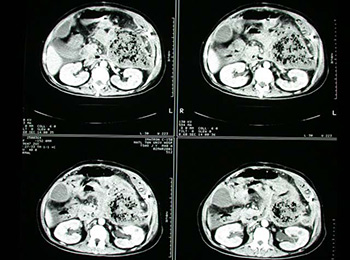

ficatului și pancreasului Seal, ca un fel de tulburări ale tractului digestiv, este diagnosticat destul de dificil și, prin urmare, necesită intervenția unui gastroenterolog cu experiență. Principalele metode de investigare a acestor patologii sunt metoda chestionarului, examinarea cu raze X și intervenție instrument. În general, această formă a bolii este usor tratabile, dar există riscul unor complicații cauzate de fiziologia pacientului. Dacă apar complicații, pacientul ar trebui să caute ajutorul unui chirurg.

Motive pentru compactarea pancreasului

Identificarea unor astfel de modificări difuze pancreatice cum să sigileze, are loc de obicei prin intermediul unui tratament cu ultrasunete. Principalele cauze ale bolilor se află în funcționarea necorespunzătoare a sistemului endocrin și regimul alimentar neregulat al pacientului, dar există și cazuri individuale legate de moștenire sau funcționarea anormală a tractului gastro-intestinal. În acest caz și într-un alt, o decizie finală cu privire la apariția focilor pancreatice, poate lua numai un specialist cu experiență.